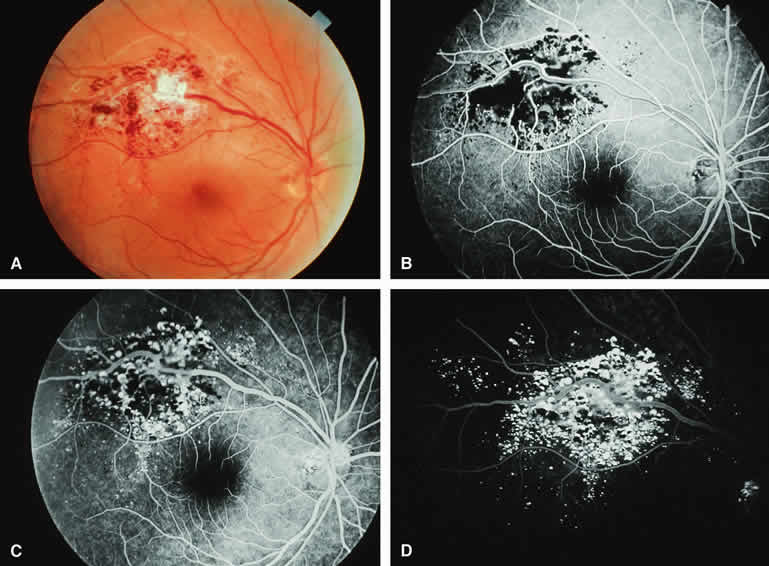

Choroidal Nevus Versus Melanoma with Prominent Lipofuscin Pigment Clumps

If one obtains a fluorescein angiogram on a small melanotic choroidal lesion (nevus versus melanoma) that has prominent clumps of lipofuscin pigment on its surface (Fig. 6), the pigment clumps appear intensely hypofluorescent throughout the study. This appearance is attributable to the complete blocking of choroidal fluorescence by the lipofuscin. ICG angiography does not show lipofuscin pigment clumps on the surface of the tumor as well as fluorescein angiography does.